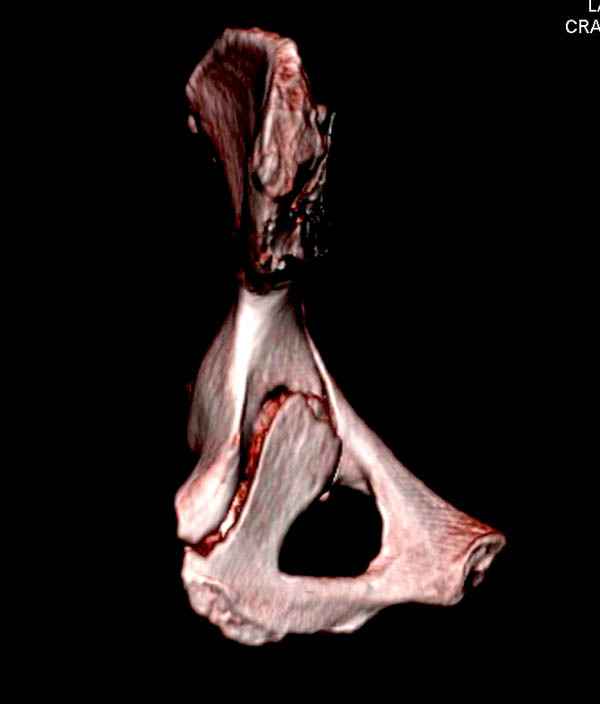

На снимке ацетабулума редко встречающийся очень низкий перелом, наверное, трудно было репозицию через один доступ? Перелом как бы замкнулся в квадрилатеральной поврехности.

Ничего такого особенного в переломе вертлужной впадины не опознал. Транстектальный перелом хорошо репонируется щипцами, установленными через седалищную вырезку.

На картинке подобный случай, только без шейки, сделано через месяц или полтора после травмы.